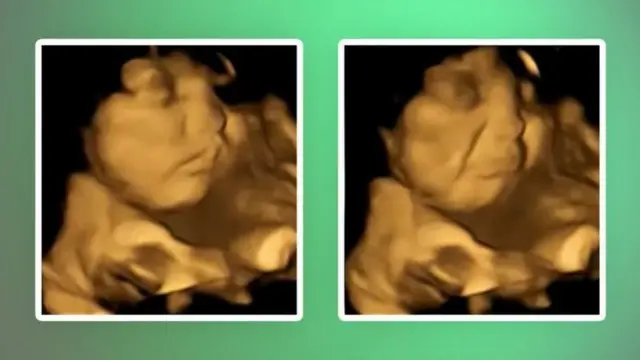

कैप्सूल देने से पहले और बाद में गर्भ में पल रहे बच्चे के चेहरे का अध्ययन किया गया और पाया गया कि जब बच्चे तक गाजर की कैप्सूल का स्वाद पहुँचा तो उसका 'हँसता चेहरा' दिखा जैसा कि तस्वीर में देखा जा सकता है.

लेकिन जब माँ को पत्तेदार हरी सब्ज़ी की कैप्सूल दी गई, तो बच्चे ने 'रोने का चेहरा' बना कर प्रतिक्रिया दी. (नीचे दी गई तस्वीर)